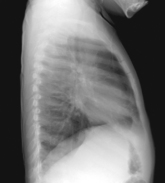

• Erect, left side against IR (unless right lateral is indicated)

• Arms raised, crossed above head, chin up

• True lateral, no rotation or tilt. Midsagittal plane parallel to IR (Don’t push hips in against the IR holder.)

• Thorax centered to CR, and to IR anteriorly and posteriorly

CR ⊥, to midthorax at level of T7. Generally IR and CR should be lowered ≈1″ (2.5 cm) from PA on average patient.